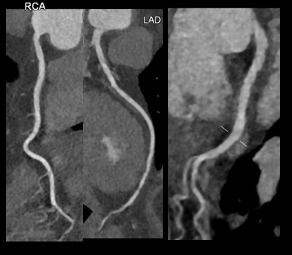

扫描速度快:得益于CT设备的快速发展,临床上使用的普遍是多层螺旋CT,这种CT机在扫描时会环绕人体快速地旋转,高端的CT机,X线管和探测器对病人完成360°旋转扫描仅仅需要0.25秒~0.625秒。

在8~16cm宽的探测器加持下,完成一次头部检查约2秒。一次胸部检查2~3秒。心脏冠脉扫描速度甚至能达到毫秒级的检查速度。